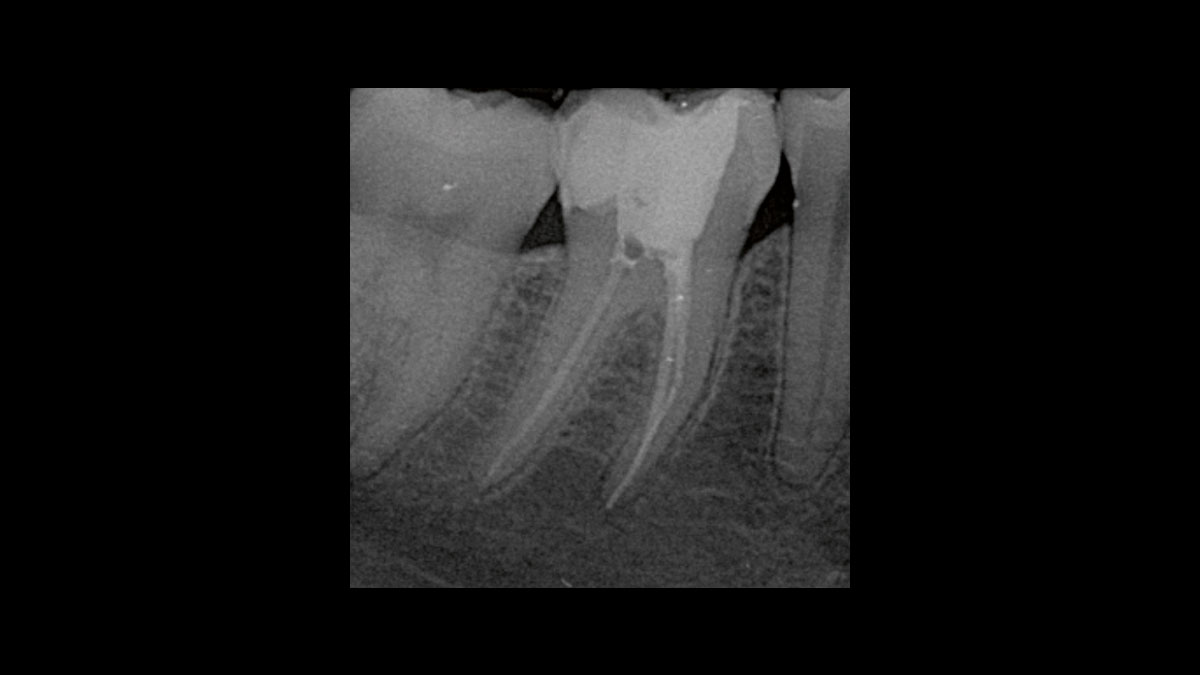

Réduction des germes endodontiques